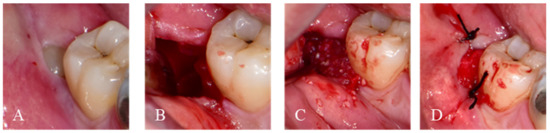

2.1.1. Immediate Graft

2.1.2. Delayed Graft